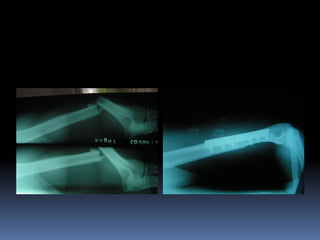

 Độ III: đặc trưng bởi tổn thương mô mềm rộng gồm cơ, da, và các cấu

trúc thần kinh mạch máu, mức độ nhiễm bẩn cao. Xương gãy thường do

chấn thương vận tốc cao dẫn đến xương gãy nát không vững. Loại này

được chia làm 3 loại nhỏ.

 Trong độ IIIA phần mềm che phủ xương còn đủ mặc dù vết thương rộng,

phần mềm bị tạo thành các vạt hoặc gay hở do chấn thương với năng

lượng cao. Loại này bao gồm các loại gãy xương nát, nhiều mảnh do

chấn thương năng lượng cao, không cần xét đến kích thước vết thương.

 Gãy hở độ IIIB là sự phối hợp giữa chấn thương rộng hoặc mất mô mềm

với tróc màng xương và lộ xương nhiễm bẩn rộng, xương gãy nát nặng

do chấn thương với vận tốc cao. Sau khi cắt lọc và tưới rửa hoàn tất, các

mảnh xương trơ ra cần phải có các vạt tại chỗ hoặc tự do để che phủ.

 Gãy hở độ IIIC là bất kỳ gãy xương hở nào có tổn thương động mạch cần

phải nối, không xét đến mức độ tổn thương mô mềm